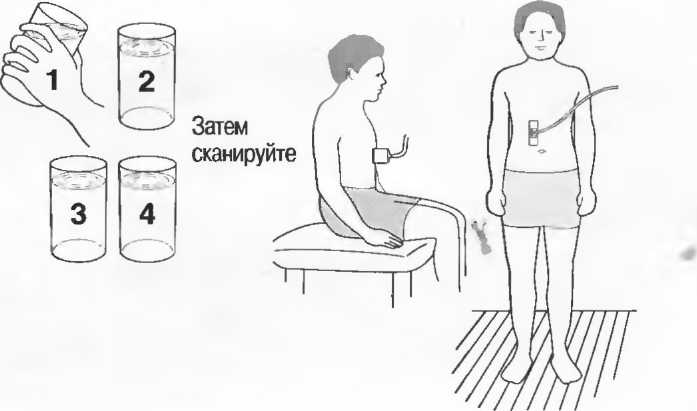

1. Подготовка

Пациент не должен пить и есть в течение 8 ч перед исследованием. Если жидкость необходима для предотвращения дегидратации, можно давать пациенту только воду. При острой симптоматике исследование можно проводить без подготовки. Детям, если позволяют клинические условия, пища и вода не даются в течение 3 ч до исследования.

При более углубленном исследовании, если нет клинических противопоказаний, может быть полезным дополнительный прием воды, особенно при исследовании поджелудочной железы, нижних отделов живота и таза.